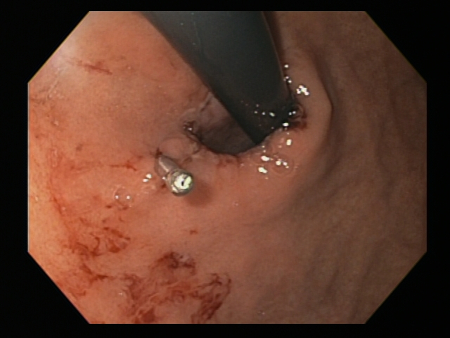

[Figure caption and citation for the preceding image starts]: Laceração de Mallory Weiss com sangramento observada em retroflexãoDo acervo pessoal de Douglas Adler; usado com permissão [Citation ends].